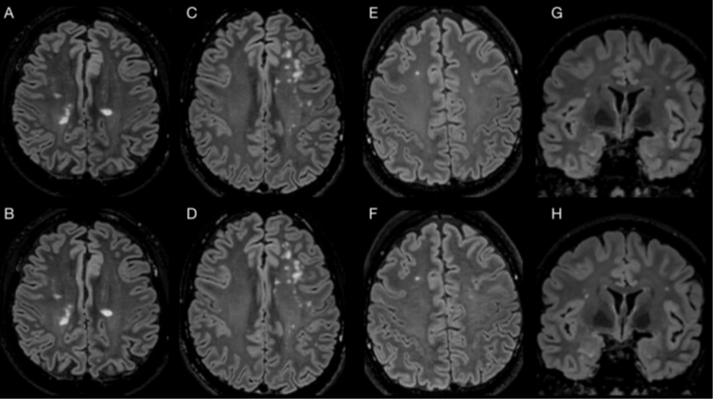

6/9 👥 Human imaging (n = 14 across multiple conditions): C-FLAIR removed skull-base hyperintensity artifacts while preserving lesion visibility in MS and white matter disease ✅ 🩻Key Clinical Point: • SNR unchanged • CNR unchanged

3/9 This is especially noticeable at 3T 🎛️ Skull base, sinuses, and temporal bone regions are notorious for off-resonance and RF variation → where FLAIR is often least trustworthy. Here, the B, F images are acquired without T2-preparation to better expose the FLAIR artifact.